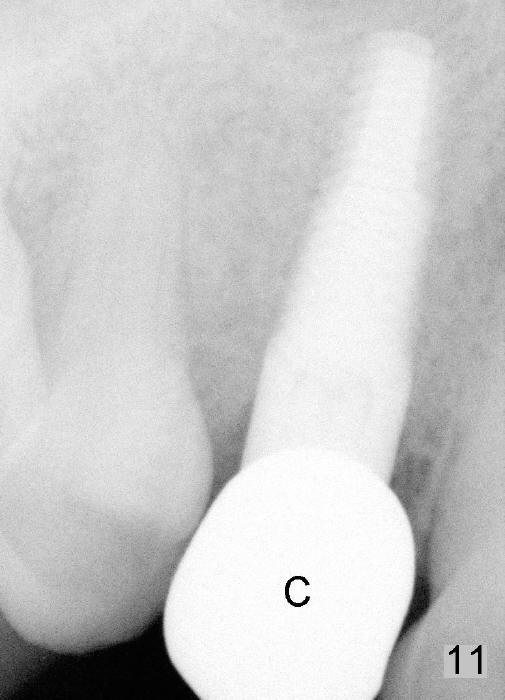

The patient returns 6 months postop for impression of a permanent restoration. The gingiva with knife-edged papillae adapts to the provisional (Fig.7). The gingiva looks healthy when the provisional is removed (Fig.8). The buccal bone resorption seems to be minimal, as compared to Fig.1,2. There is no bone loss between immediately postop (Fig.9 I; implant), 4.5 months postop (Fig.10 A: abutment), 4 and 7 months post cementation (Fig.11,12 C: crown). Soft and hard tissue morphology remains normal 7 months post cementation (Fig.13). No bone loss is observed 15 months post cementation (Fig.14). The papillae (Fig.15) and bone (Fig.16,17) remain stable 29 months post cementation.